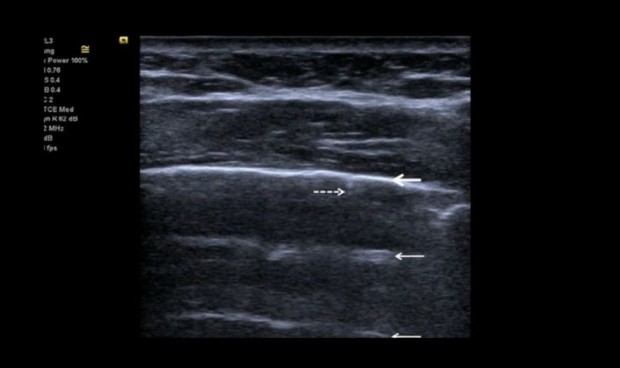

Seguimiento de un paciente de UCI con neumonía Covid-19.

“Debido al desarrollo continuo de su estado clínico, los pacientes ingresados por Covid grave necesitan con frecuencia imágenes de tórax. La ecografía torácica puede hacer una contribución sustancial, ya que permite el examen directo de cabecera del pulmón y el espacio pleural. Estos pacientes muestran neumonía intersticial bilateral difusa, con lesiones irregulares y parcheadas distribuidas principalmente en la periferia del pulmón”, explican los autores en un artículo publicado en SpringerOpen.

En este contexto, los expertos destacan que la ecografía pulmonar sirve para evaluar rápidamente la gravedad de la neumonía por SARS-CoV-2, ya que rastrea la evolución de la enfermedad durante el seguimiento y monitorea las maniobras de reclutamiento pulmonar. Además, argumentan que la ecografía puede rastrear la respuesta a la ventilación en decúbito prono y el control de la terapia de membrana extracorpórea.